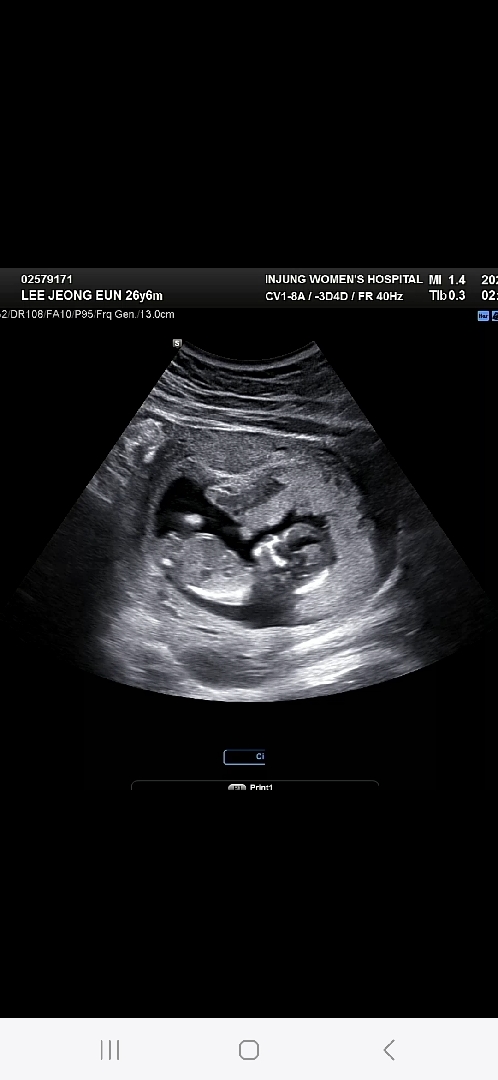

각도법 고수님들 봐주세요!!

알수있을까요?!?!?

갠적으로 조심스레 딸에 한표요!